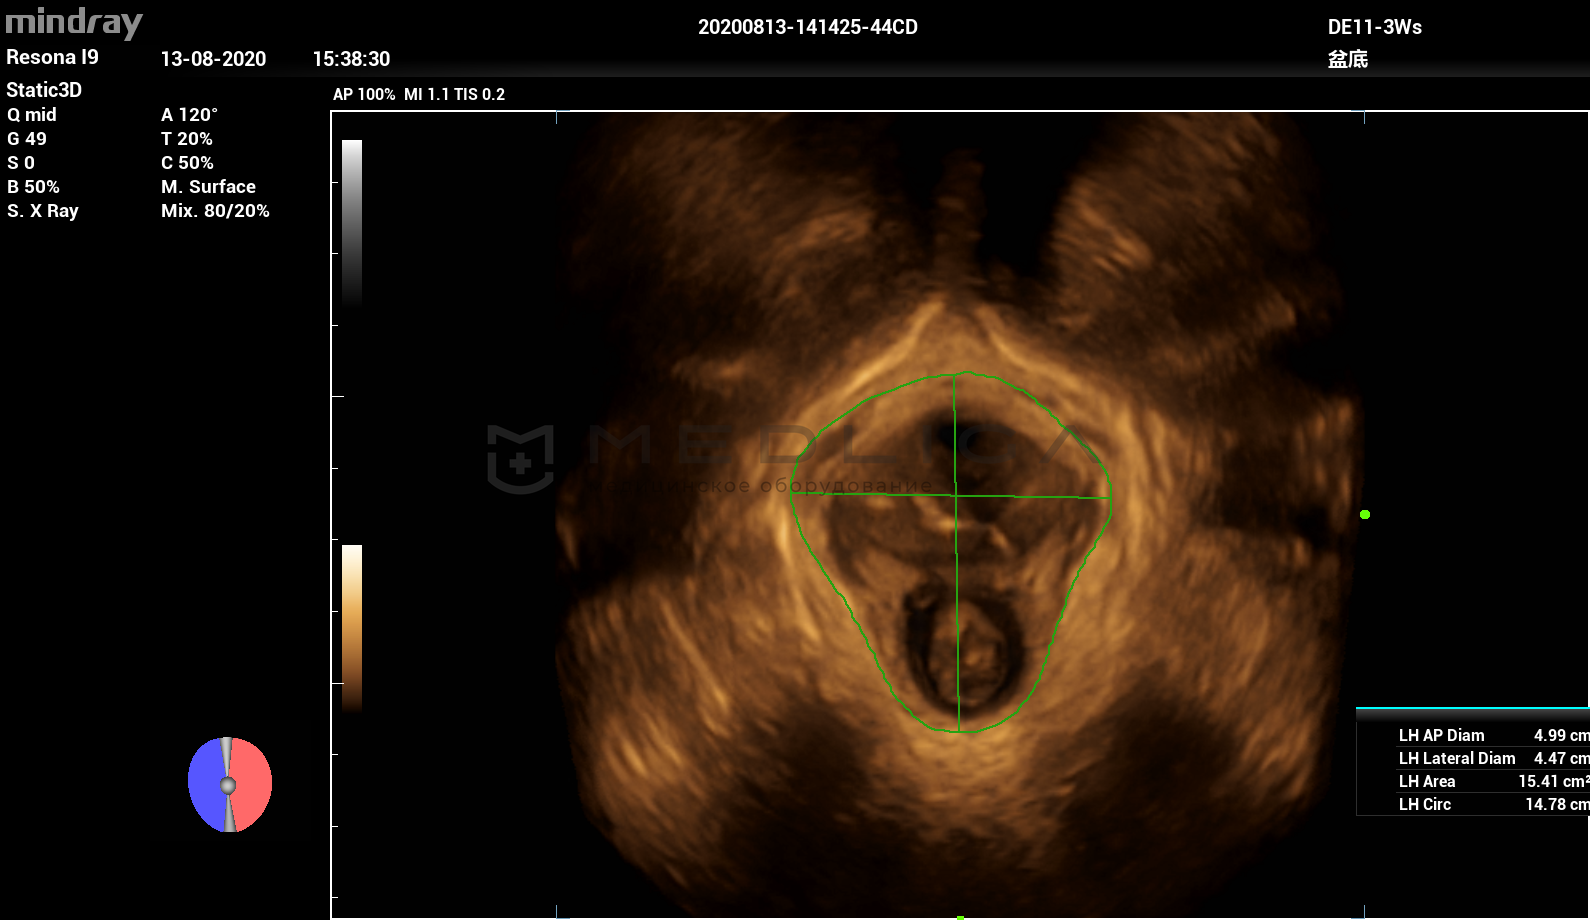

Программное обеспечение для автоматических измерений параметров и оценки функции мышц тазового дна.

Smart Pelvic - новое решение, позволяющее значительно упростить диагностическую процедуру и свести к минимуму время исследования функций мышц тазового дна. Благодаря чрезвычайно простому пользовательскому интерфейсу, программа генерирует стандартную систему координат и автоматически просчитывает все связанные измерения в течение нескольких секунд.